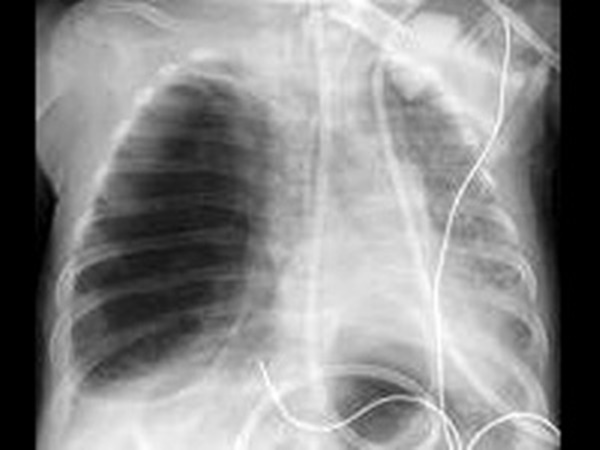

ചികത്സകള്

എക്സ്റേയാണ് രോഗം കണ്ടുപിടിക്കാനുള്ള എളുപ്പമാര്ഗം. രക്തപരിശോധനയും നടത്താറുണ്ട്.